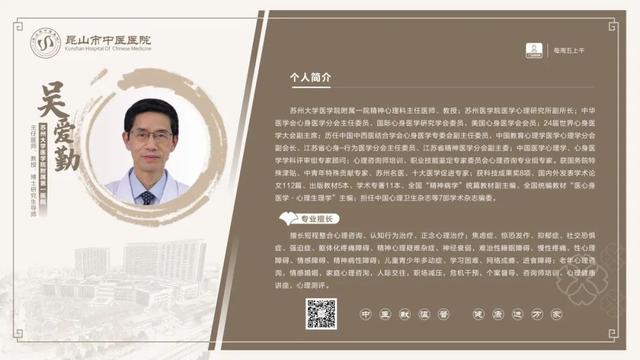

6��23��-6��29�������dz���ר�ҽ���